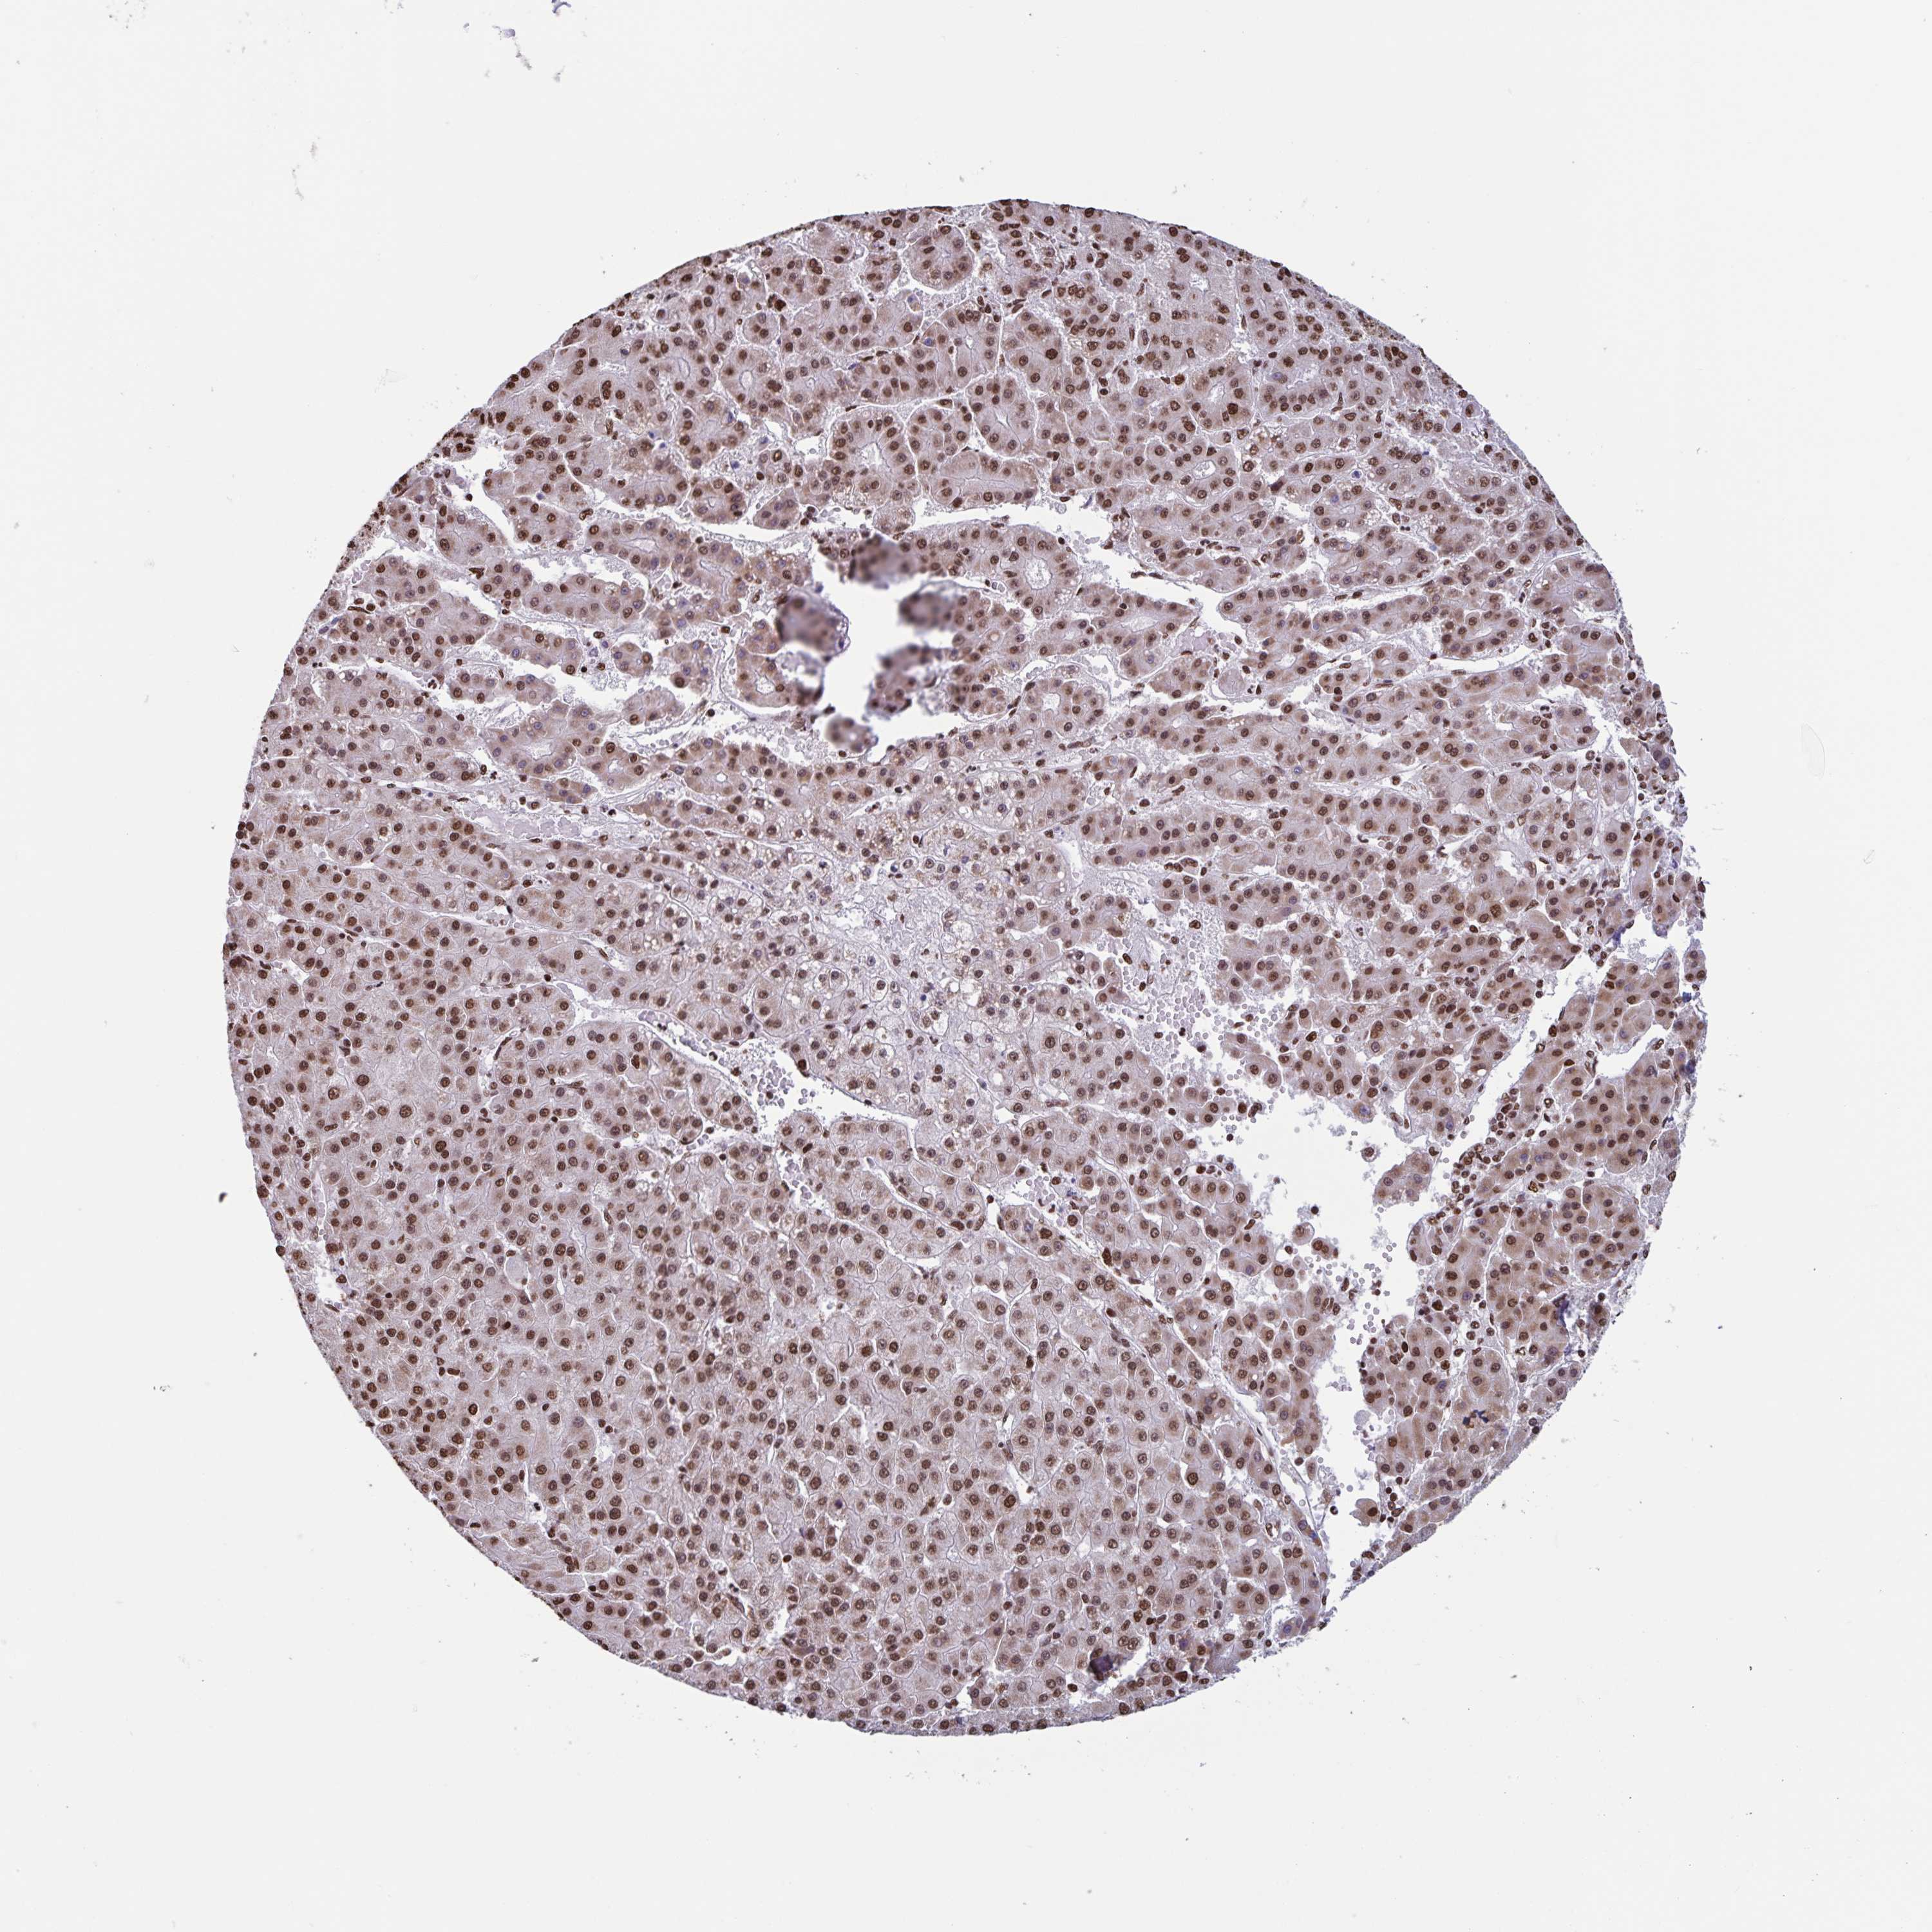

LIVER CANCER - Protein expressioni

A mouse-over function shows sample information and annotation data. Click on an image to view it in a full screen mode. Samples can be filtered based on level of antibody staining by selecting one or several of the following categories: high, medium, low and not detected. The assay and annotation is described here.

Antibody stainingi

Antibody staining in the annotated cell types in the current human tissue is reported as not detected, low, medium, or high, based on conventional immunohistochemistry profiling in selected tissues. This score is based on the combination of the staining intensity and fraction of stained cells.

Each image is clickable and will lead to virtual microscopy that enables deeper exploration of all samples and also displays staining intensity scores, fraction scores and subcellular localization as well as patient and tissue information for each sample.

Antibody HPA054422

Antibody HPA060360

Staining

High

Medium

Low

Not detected

Intensity

Strong

Moderate

Weak

Negative

Quantity

>75%

75%-25%

<25%

None

Location

Nuclear

Cytoplasmic/membranous

Cytoplasmic/membranous,nuclear

Carcinoma, Hepatocellular, NOS

Cholangiocarcinoma